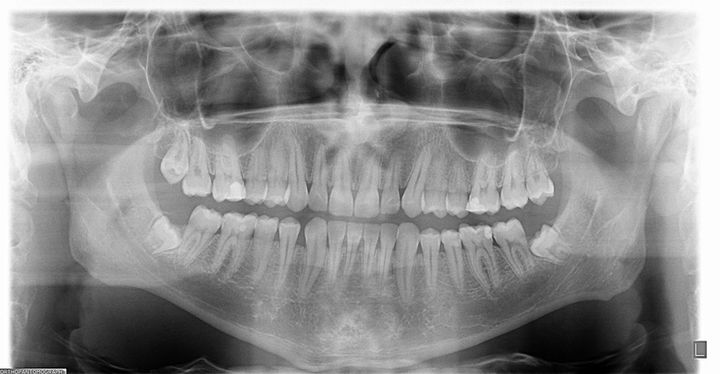

Resim3.1.jpg

Resim3.jpg